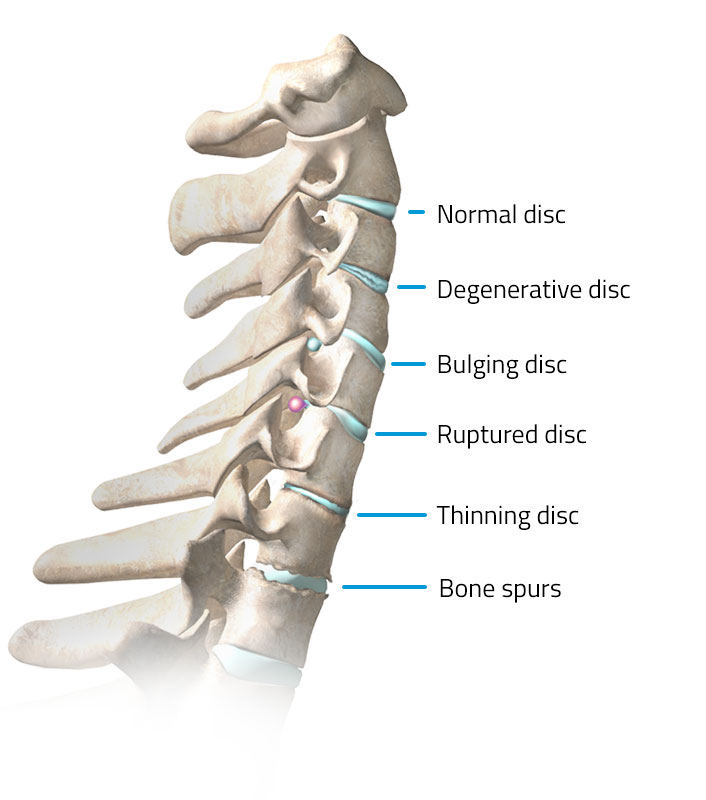

Disc In Neck: Bulging Disc In Neck With Bone Spurs

Bulging Disc | Bulging disc, Spondylolisthesis, Cervical

Bone spurs in neck (cervical osteophytes): Causes, symptoms, diagnosis …

Arthritis (Spine) And Bone Spurs

Dissecting Spinal Degeneration in the Neck (Neck Pain Support Blog)